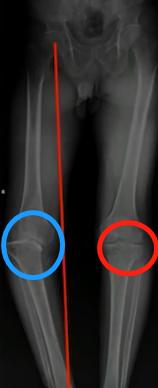

看上图这个病人,左膝是痛风性关节炎的患侧,右膝相对正常。左右膝对比就可以看出,左膝因为痛风性关节炎的影响,关节力线已经不好,即髋膝踝3点的连线不通过,膝关节,出现严重内翻膝的情况。而且关节间隙(圆圈处)已经不平衡,导致软骨磨损严重。且患者出现部分骨缺损情况,就是这个骨头没有了,无法承重了。